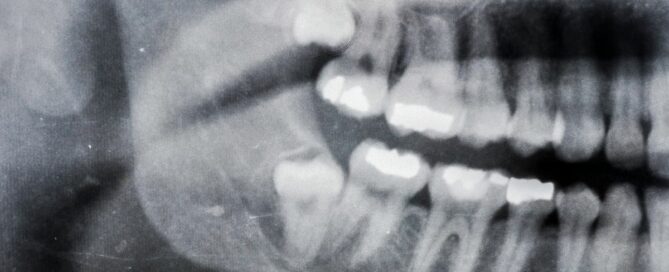

Wisdom tooth extraction is a standard dental procedure to remove [...]